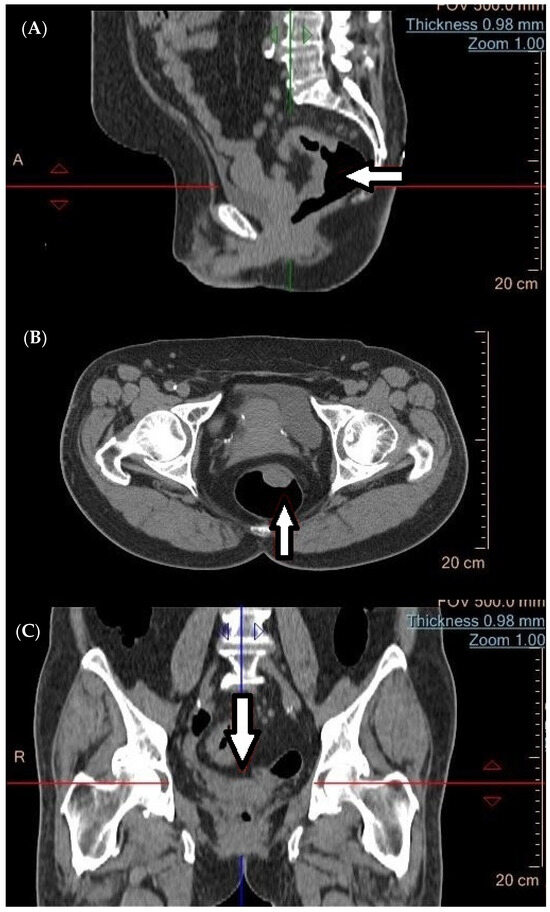

Effect of Fluorescence Lymph Node Mapping on Improving Diagnostic Values of CT D3 Lymph Node Staging for Right-Sided Colon Cancer

Cancers 2024, 16(20), 3496; https://doi.org/10.3390/cancers16203496 - 16 Oct 2024

Background/Objectives: This study evaluated the impact of fluorescence lymph node mapping (FLNM) using indocyanine green (ICG) on the diagnostic accuracy of preoperative computed tomography (CT) in right-sided colon cancer. Methods: A total of 218 patients who underwent laparoscopic right hemicolectomy with D3 lymph [...] Read more.

Background/Objectives: This study evaluated the impact of fluorescence lymph node mapping (FLNM) using indocyanine green (ICG) on the diagnostic accuracy of preoperative computed tomography (CT) in right-sided colon cancer. Methods: A total of 218 patients who underwent laparoscopic right hemicolectomy with D3 lymph node dissection (LND) were analyzed: 86 patients in the FLNM group and 132 in the conventional surgery group. The FLNM technique allowed for enhanced intraoperative visualization of lymph node (LN) and more precise dissection, improving the identification of metastatic LNs. The diagnostic value of preoperative CT staging was assessed in both the FLNM and control groups by calculating the apparent prevalence, true prevalence, sensitivity, specificity, positive predictive value (PPV), negative predictive value, positive likelihood ratio (PLR), negative likelihood ratio, false positive and false negative proportions, and accuracy. Results: FLNM increased the accuracy of CT staging for detecting D3 LN metastasis in advanced cancer cases, with a higher PPV, PLR, and accuracy. In the FLNM group, the false-positive rate was significantly reduced, and the specificity was higher compared to the control group. Multivariate analysis identified FLNM as an independent factor associated with improved D3 LN metastasis detection. These findings suggest that incorporating FLNM into surgical procedures enhances the diagnostic value of preoperative CT by improving the precision of LND, particularly in patients with advanced colon cancer. Conclusions: The use of FLNM for D3 LND enhances the diagnostic accuracy of cN staging in right-sided colon cancer by improving surgical precision. Full article